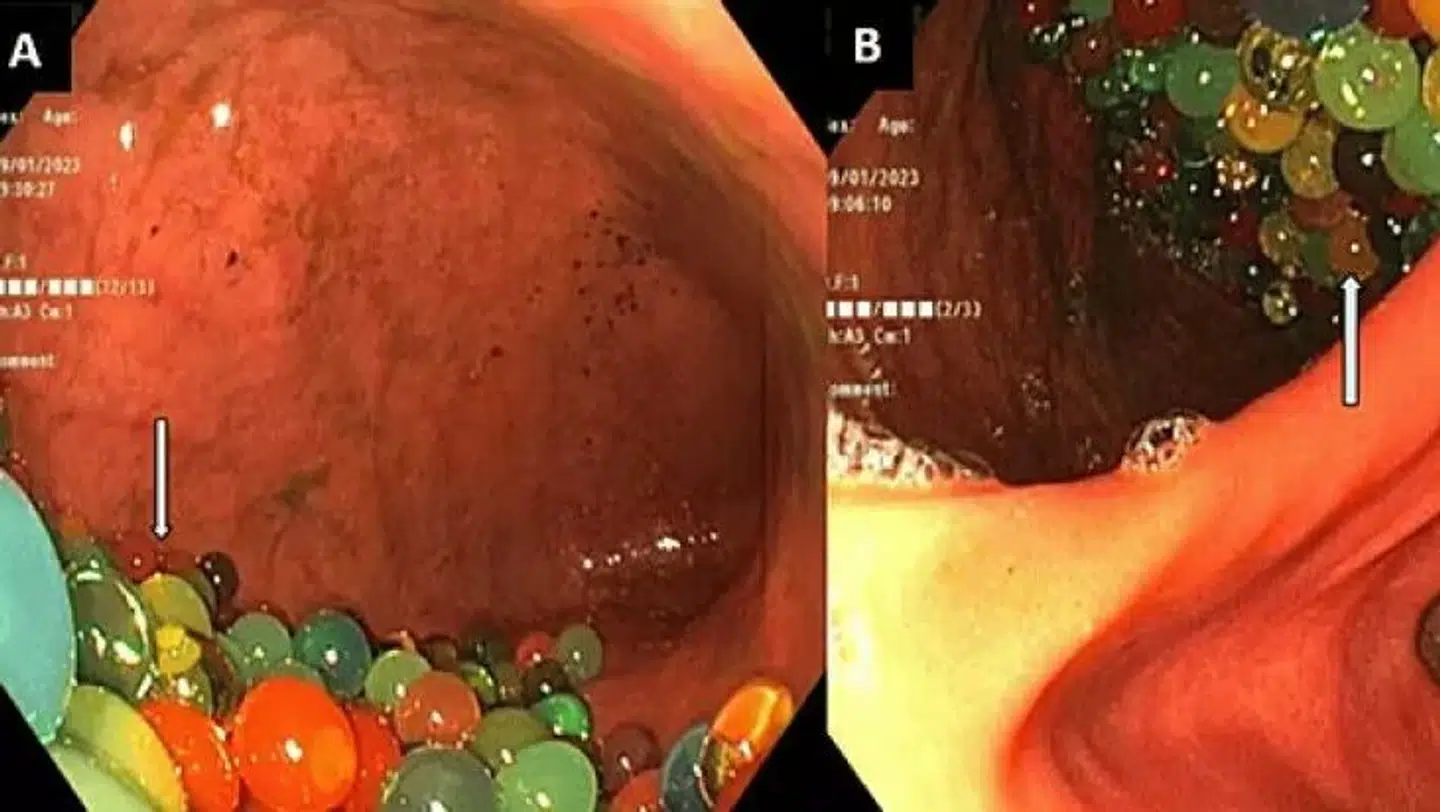

I CT-scanningen af drengen viste der sig »utallige små, runde perler i hele mave-tarmregionen«, og her fik lægerne fjernet mellem 50 og 70 af perlerne gennem en såkaldt gastroskopi.